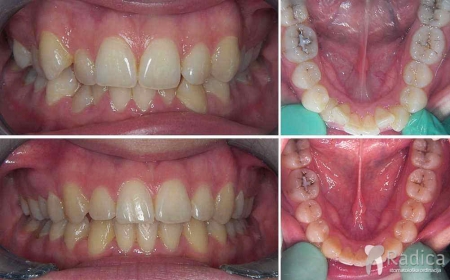

Primjeri fiksne ortodontske terapije dubokog zagriza:

Primjer terapije kod dubokog zagriza: